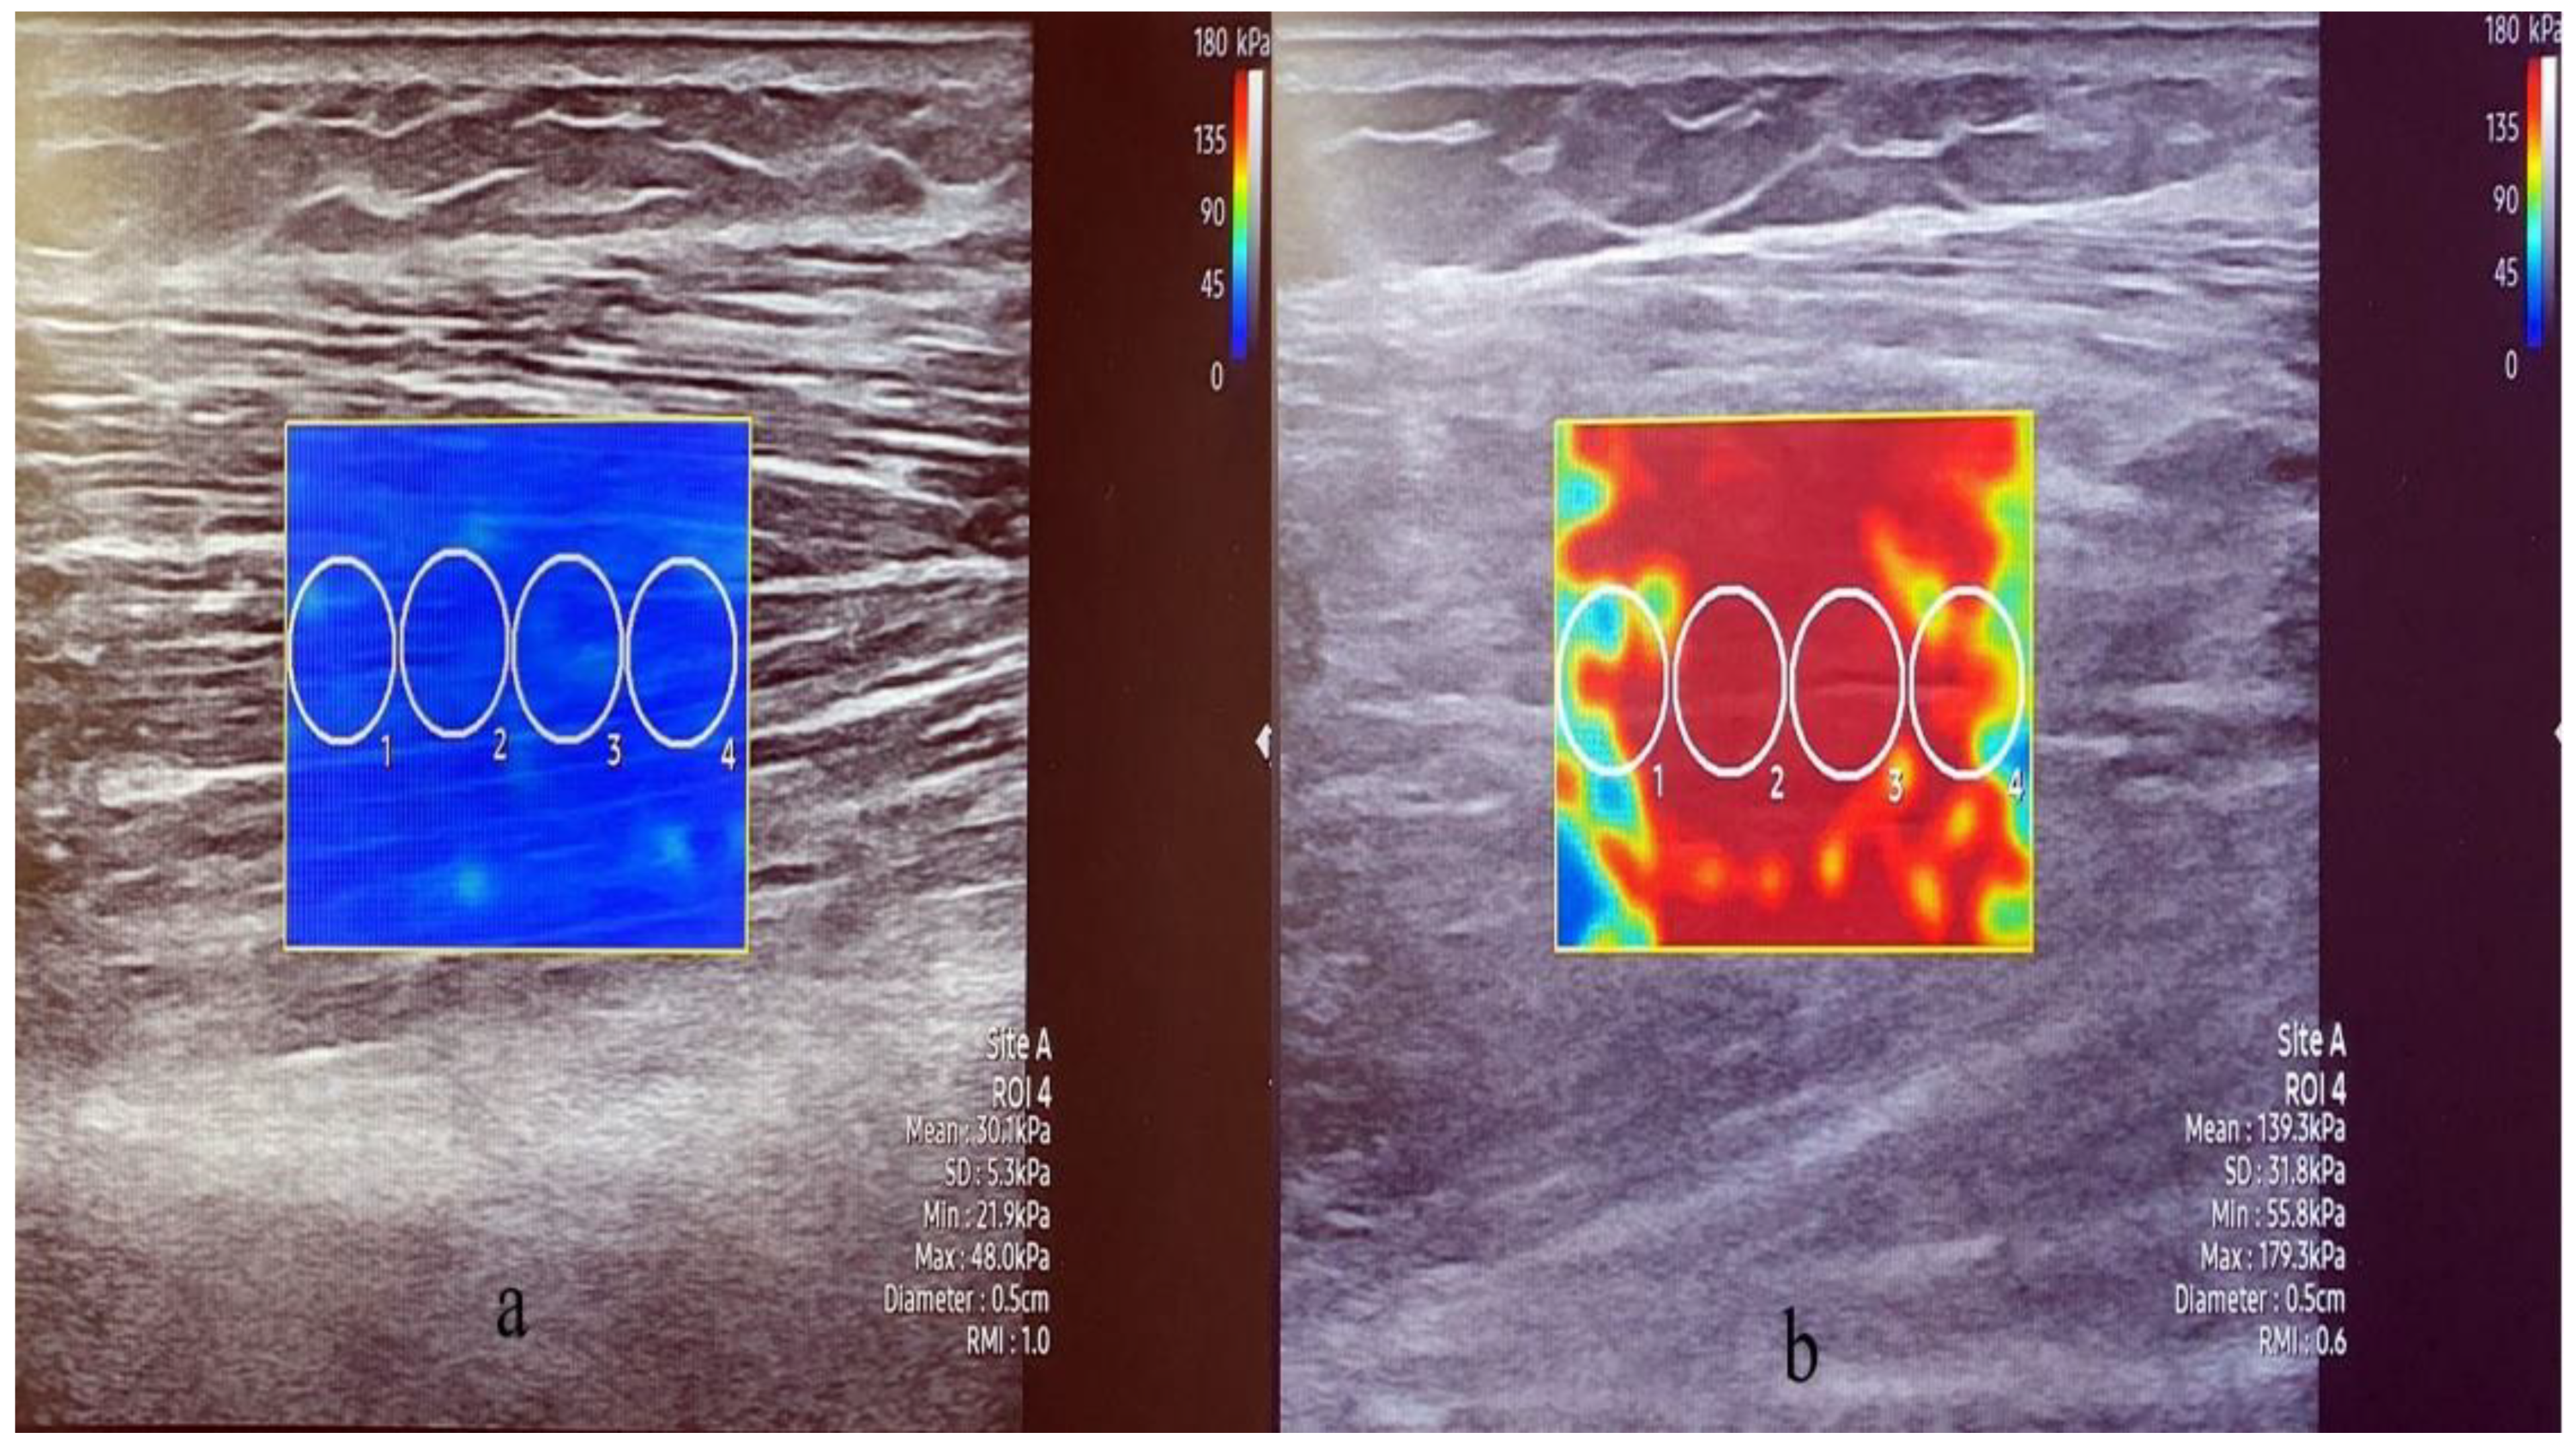

2.3.4. Stiffness and Thickness of the Muscle

- Lee, Y.; Kim, M.; Lee, H. The measurement of stiffness for major muscles with shear wave elastography and myoton: A quantitative analysis study. Diagnostics 2021, 11, 524. [Google Scholar] [CrossRef] [PubMed]